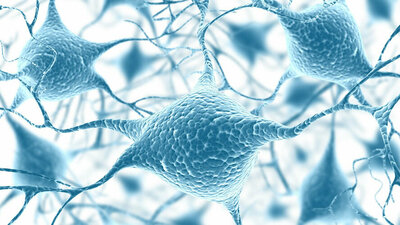

Diabetische Neuropathie

Nervenschäden sind eine häufige Diabetesfolge. Heilbar ist eine Neuropathie nicht. Die Therapie zielt vor allem darauf ab, ein Fortschreiten zu vermeiden und die Beschwerden zu lindern. zum Artikel

Sensomotorische Neuropathie

Erhöhte Blutzuckerwerte bei Diabetes können die Nerven schädigen, die für Bewegungen und Empfindungen zuständig sind zum Artikel

Nervensystem

Das menschliche Nervensystem unterteilt sich in einen zentralen und einen peripheren Teil. Bei Diabetes können Nervenfunktionen gestört sein zum Artikel